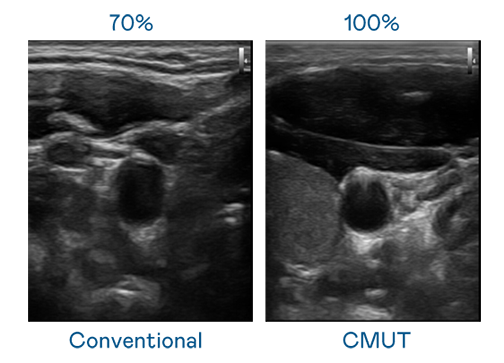

CMUT 技術是一種用電容式微機電元件來產生超音波訊號的技術。與傳統 PZT 壓電式技術相比,CMUT 頻寬增加 30%,更寬頻的超音波訊號讓影像解析度大幅提升,是實現高影像品質醫療超音波掃描、促進精準醫療發展的關鍵技術。

超音波影像的解析度高低,首先取決於探頭能發出的訊號頻寬。YABO鸭脖 CMUT 可提供高清晰的超音波訊號,提供高頻寬、高靈敏度、影像紋理細節更高的超音波影像,協助醫護人員縮短影像判讀時間及利用精準的醫療影像進行診斷。